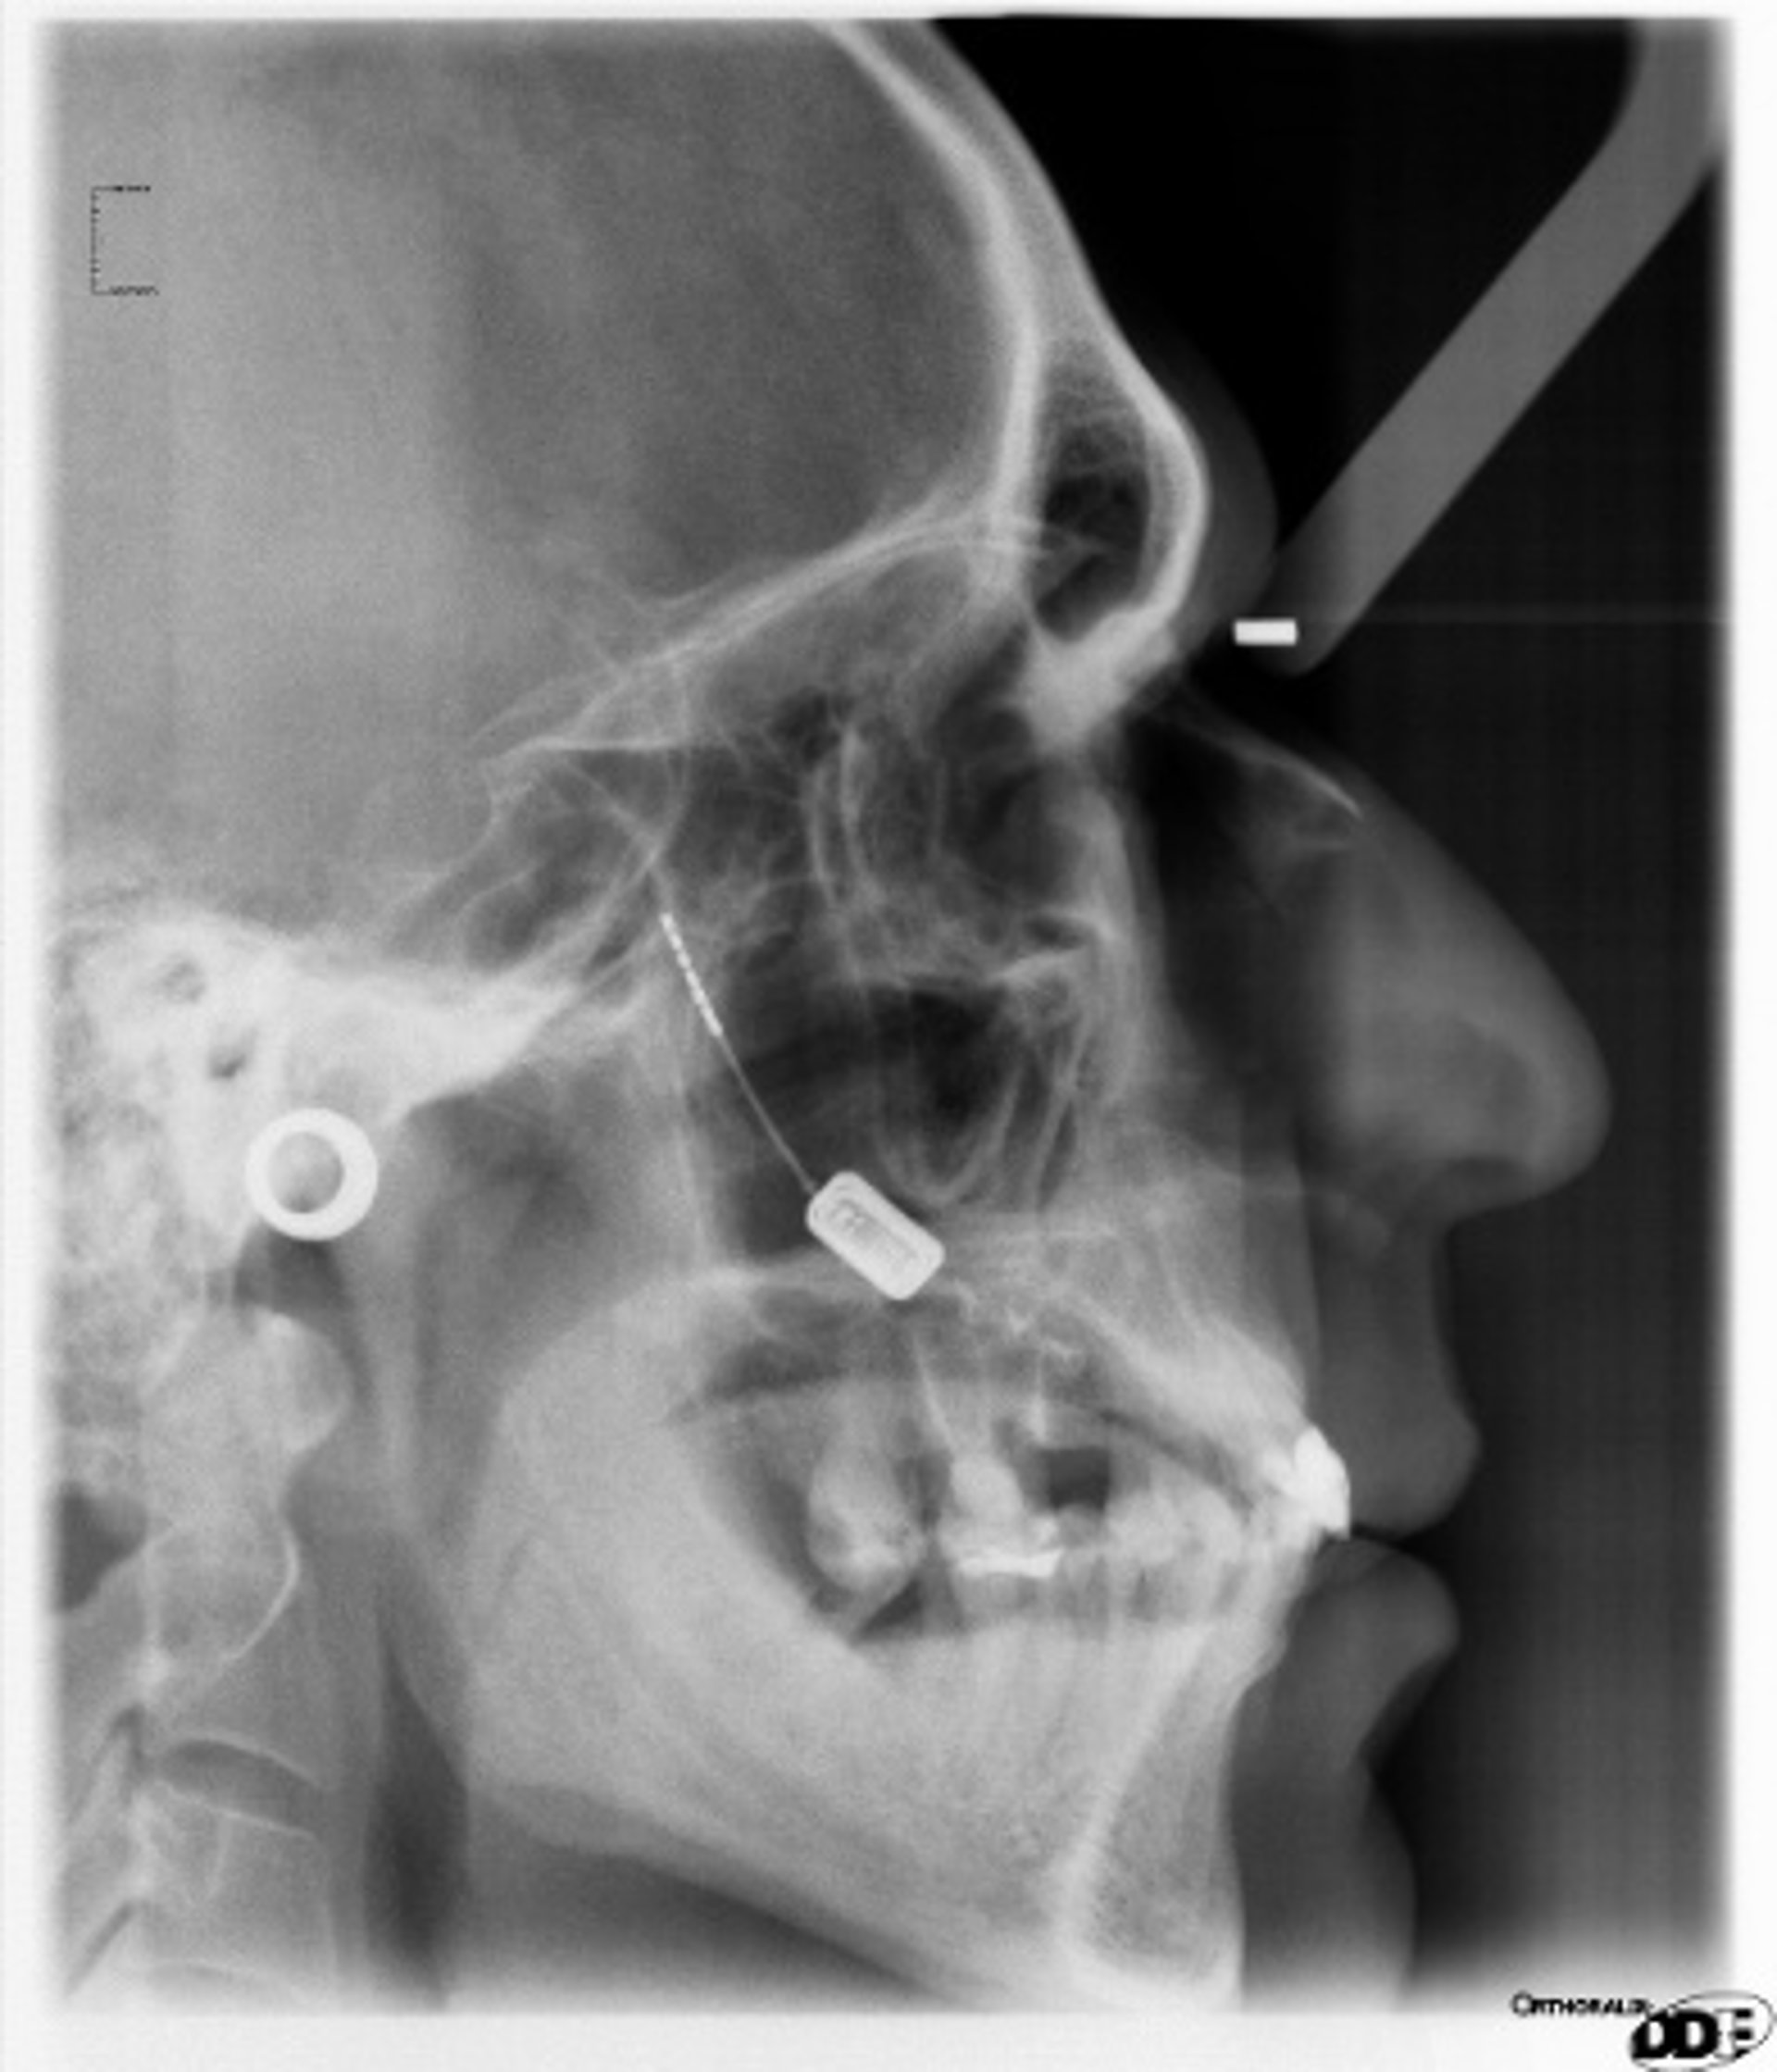

El sistema empleado consiste en un dispositivo que se ha diseñado específicamente para tratar el dolor de cabeza severo y que estimula el ganglio esfenopalatino, con un controlador remoto de mano (un mando) que maneja el propio paciente proporcionando estimulación cuando tiene dolor.

"El estimulador --ha señalado el doctor Láinez-- es aproximadamente del tamaño de una almendra y se coloca a través de una incisión quirúrgica en el maxilar superior sin dejar cicatrices externas; el uso de un mando poco más grande que un teléfono móvil permite a los pacientes desactivar la terapia de estimulación cuando ya no hay dolor".